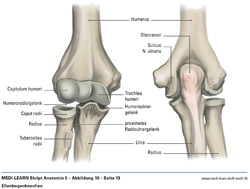

• Ellenbogenknochen